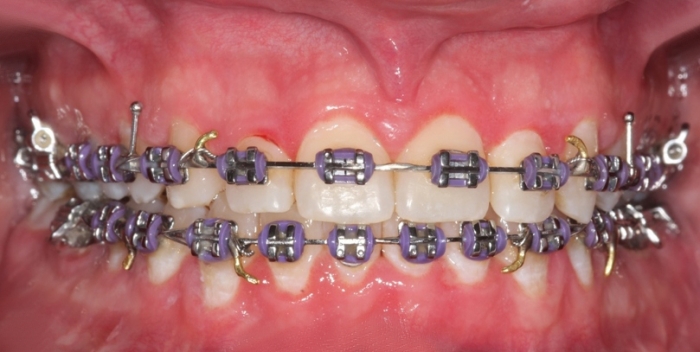

Mordida inicial